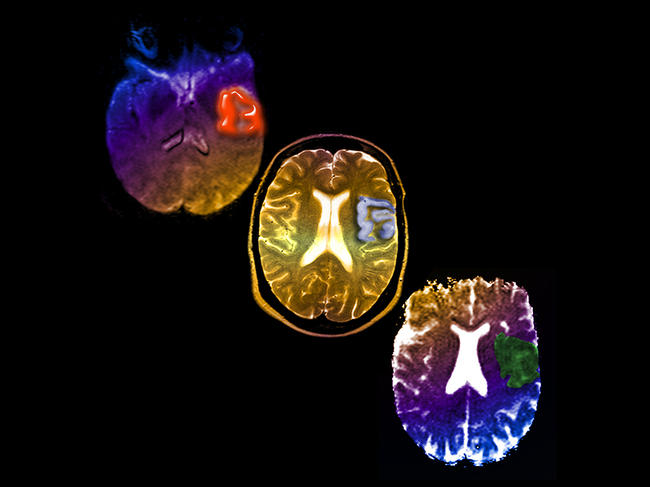

Maîtrise de la langue, milieu social, homme ou femme… la Journée mondiale de l’accident vasculaire cérébral (AVC), le 29 octobre, est l’occasion de rappeler que les inégalités sociales de santé jouent un rôle non négligeable dans la prise en charge des patients, au-delà des critères purement biologiques ou médicaux. Cet article est paru dans Le Journal du CNRS.